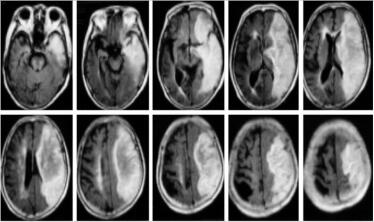

颅脑磁共振弥散加权成像(diffusion weighted imaging,DWI):①左侧大脑中动脉供血区急性期梗死灶。左侧颈内动脉海绵窦段所见,考虑有血栓形成。②脑干、双侧基底节区及丘脑双侧半卵圆中心多发陈旧性梗死灶(图1)。

图1 DWI显示左侧额、颞、顶、枕叶皮质下病灶为高信号